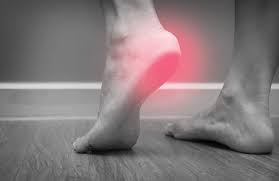

So, if you have a heel spur and notice pain at the back of the heel, you probably have achilles tendinitis. Inflammation and swelling at the front of the heel. Aug 28, 2020 · a heel spur is a calcium deposit causing a bony protrusion on the underside of the heel bone. What are the symptoms of a bone heel spur? Healthprep.com has been visited by 100k+ users in the past month Get superior comfort & revolutionary support! Many people have heel spurs without any symptoms at all, and experts are still trying to figure out exactly how spurs relate to heel pain. If you have pain in your hindfoot, you might be a heel spur. What are the symptoms of heel spurs? The forefoot (toes), the midfoot (arch), and the hindfoot (heel and ankle). It's a common assumption — and a heel spur can cause foot discomfort. Nov 22, 2019 · symptoms of heel spurs may include: If the pain is on the bottom of the heel, plantar fasciitis is most likely the reason.

However, only 50% of people who have heel spurs actually feel any pain because of it. How painful are heel spurs? What is the treatment for heel spur? Swelling at the front of your heel. The forefoot (toes), the midfoot (arch), and the hindfoot (heel and ankle). The affected area may also feel warm to the touch. So, if you have a heel spur and notice pain at the back of the heel, you probably have achilles tendinitis. It's a common assumption — and a heel spur can cause foot discomfort.

It's a common assumption — and a heel spur can cause foot discomfort. What is the treatment for heel spur? Healthprep.com has been visited by 100k+ users in the past month A dull ache in the heel throughout the day. Point of tenderness at the bottom of the heel that makes it hard to walk barefoot. However, only 50% of people who have heel spurs actually feel any pain because of it. The forefoot (toes), the midfoot (arch), and the hindfoot (heel and ankle). Kuru® heel spur shoes mold to feet. So, if you have a heel spur and notice pain at the back of the heel, you probably have achilles tendinitis. Swelling at the front of your heel. The affected area may also feel warm to the touch. Discover the early warning signs and symptoms of a heel spur to be aware of now. Many people have heel spurs without any symptoms at all, and experts are still trying to figure out exactly how spurs relate to heel pain.

See full list on wikihow.com These symptoms may spread to the arch of your foot. There are three main parts of your foot's anatomy: Aug 28, 2020 · a heel spur is a calcium deposit causing a bony protrusion on the underside of the heel bone. If the pain is on the bottom of the heel, plantar fasciitis is most likely the reason.